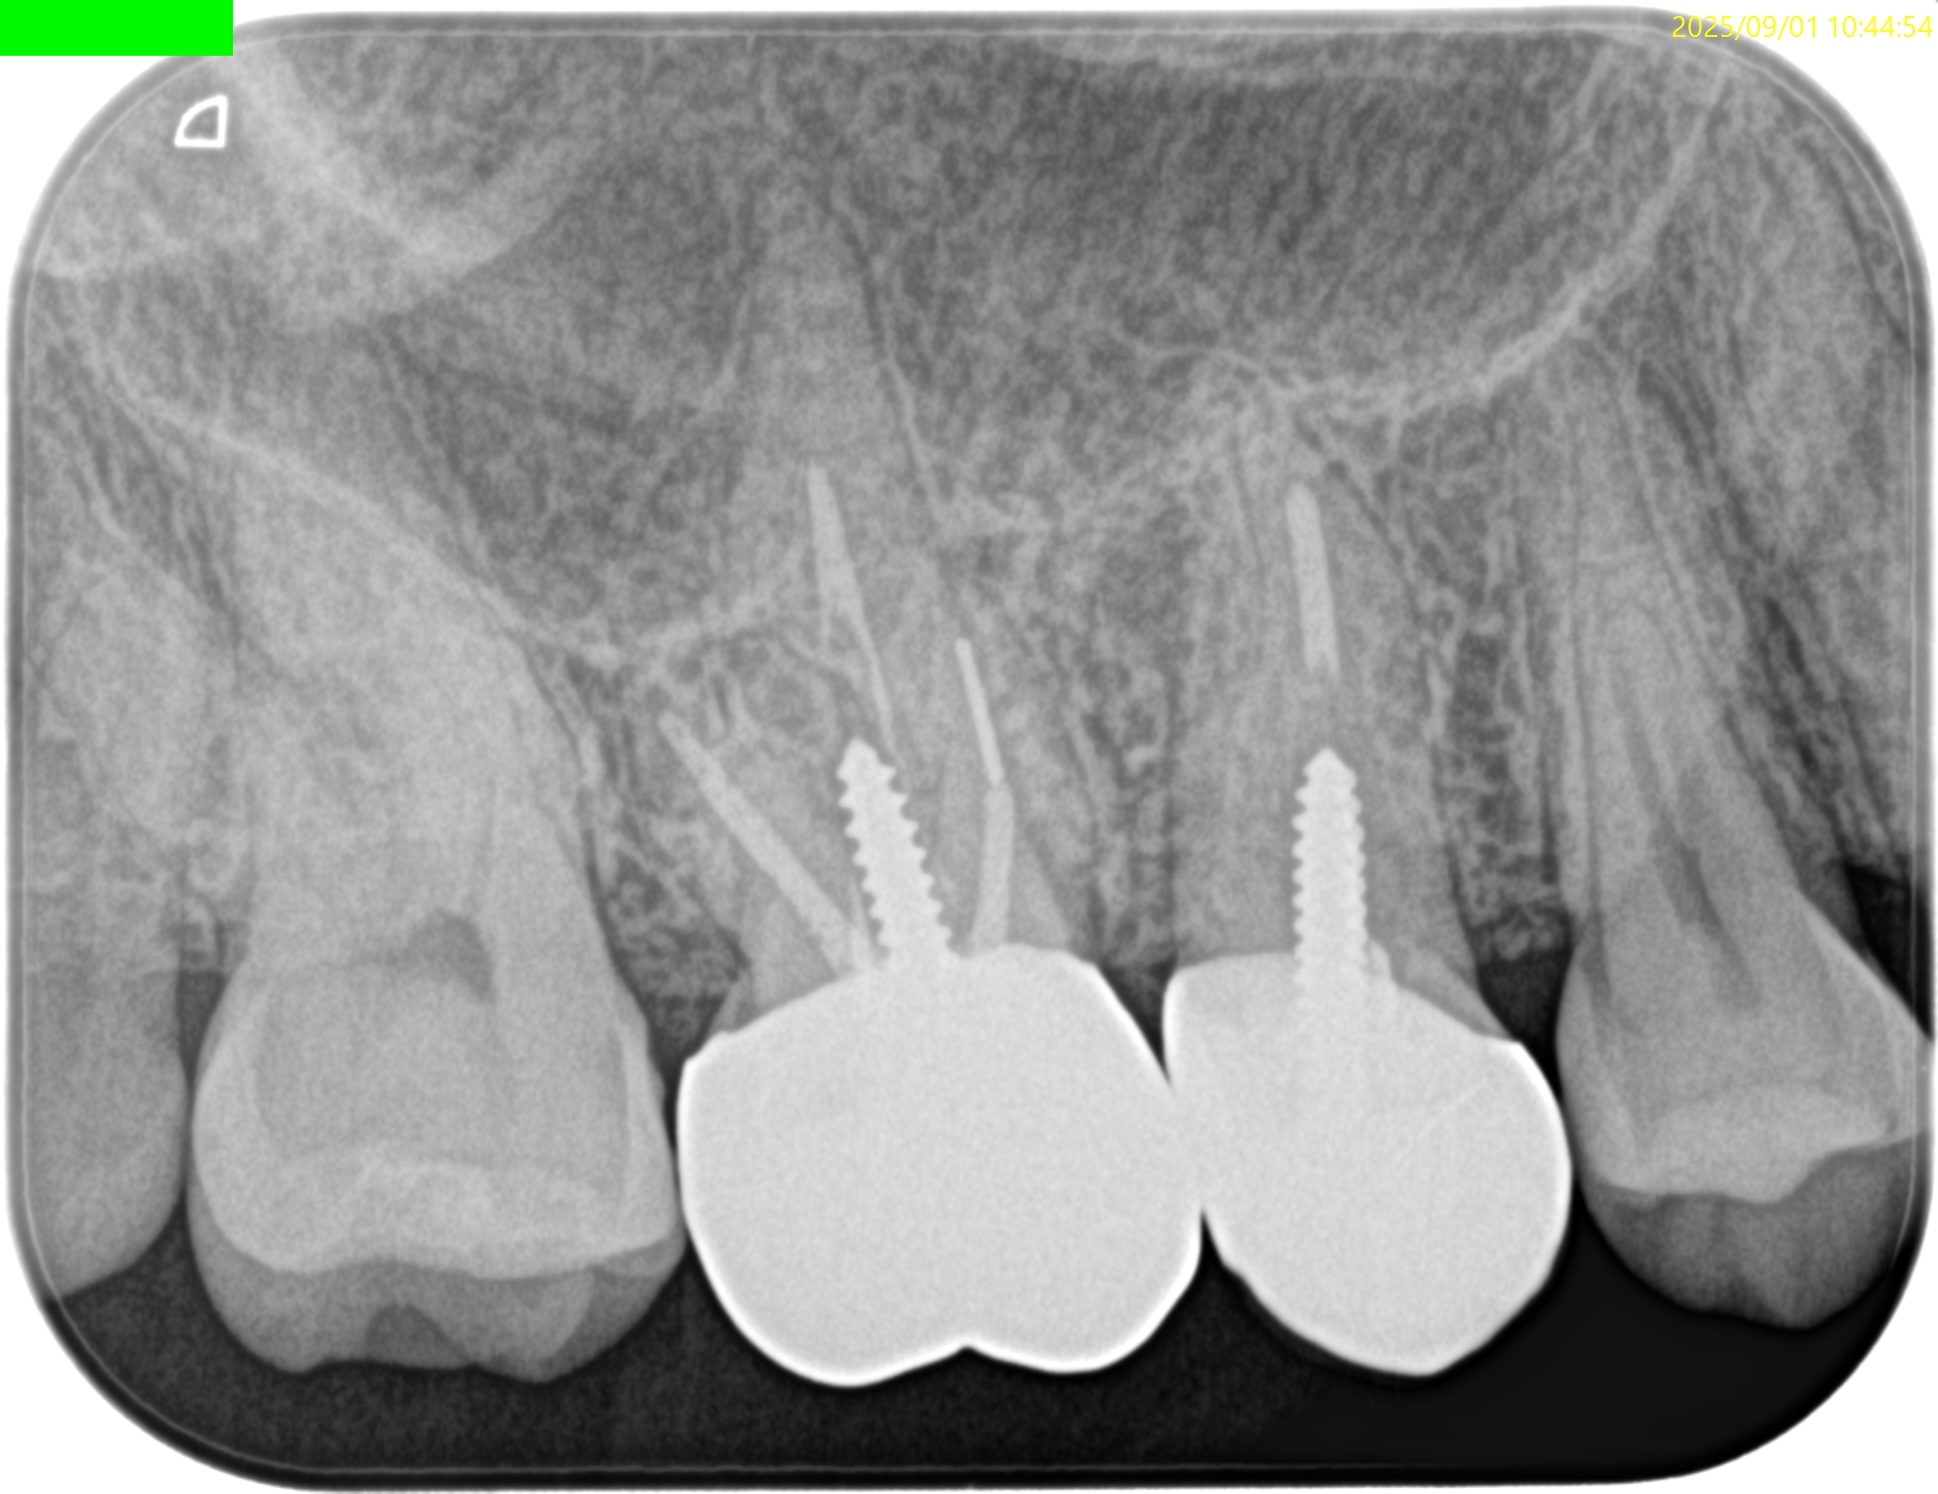

PA(2025.9.1)

#3

MB

DB

P

#4

B

#3のMBにはFileが折れ込んでいる。

#4はP根管が未着手だ。